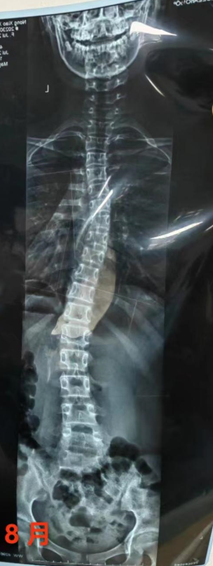

案例二

2023年8月

2023年11月